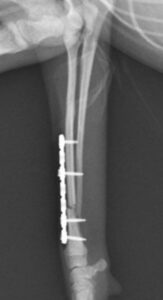

右前腕骨折のポメラニアンちゃんが来院されました。橈尺骨骨折は動物病院では一番よくある骨折です。ロッキングプレートであるTAITAN1.2で対応しました。治りも順調で元気に帰りました。よかったね。